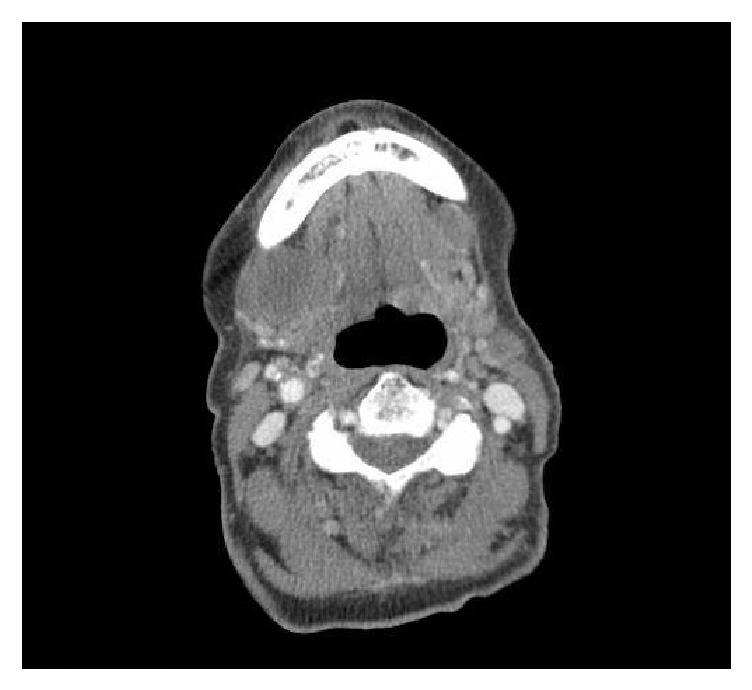

Angiosarcoma is a cancer that is derived from endothelial cells that line blood vessels and lymphatic channels. Cutaneous angiosarcoma can appear anywhere on the skin and the clinical presentation is highly variable. Most cases appear on the scalp and face de novo. Our case describes a 91-year-old female with cutaneous scalp angiosarcoma. Our case serves to remind physicians that an abnormal skin finding in older adults should raise their index of suspicion for angiosarcoma and an early biopsy should be performed.

血管肉瘤是一种起源于血管和淋巴管内衬内皮细胞的癌症。皮肤血管肉瘤可出现在皮肤上的任何部位,临床表现高度多变。大多数病例最初出现在头皮和面部。我们的病例描述了一位91岁患有头皮皮肤血管肉瘤的女性。我们的病例旨在提醒医生,老年人皮肤出现异常表现时应提高对血管肉瘤的怀疑指数,并应尽早进行活检。